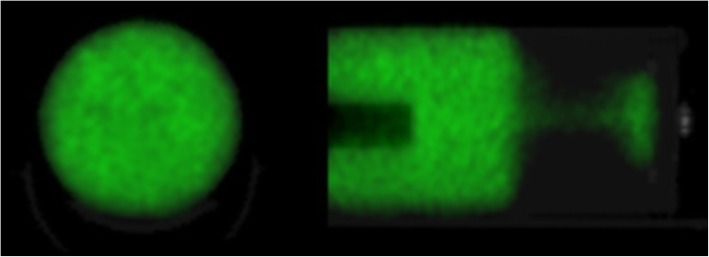

A NEMA-NU4 micro-PET image quality phantom (main volume = 20 mL) was filled with a known activity of 8.2 MBq 152Tb in an aqueous solution resulting in an actual activity concentration (Ac,bg) of 410 kBq/mL (Fig. 1). For phantom imaging and reconstruction, we adopted the same camera settings described above for animal imaging. Quantitative imaging data were obtained by multiplying the measured signal by the scaling factor: SF = (Sbg/Ac,bg)−1, where Sbg is the average signal measured in the phantom background region.

Fig. 1.

NEMA-NU4 phantom filled with a uniform activity of 152Tb, used to derive the count/activity calibration factor